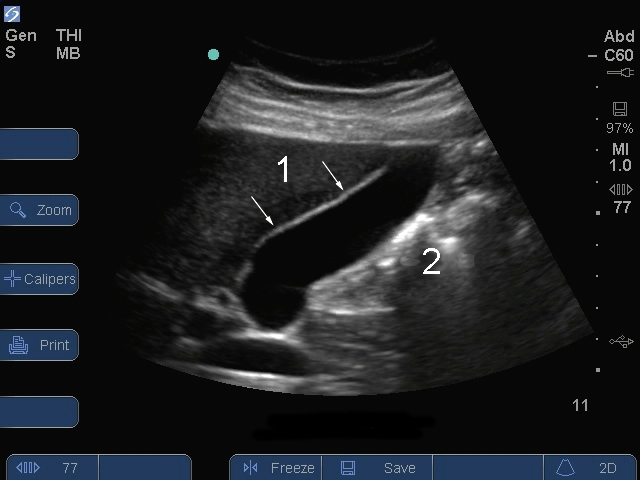

S Series : Vue longitudinale de la vésicule biliaire 2

1. Paroi antérieure de la vésicule biliaire

2. Gaz dans les intestins